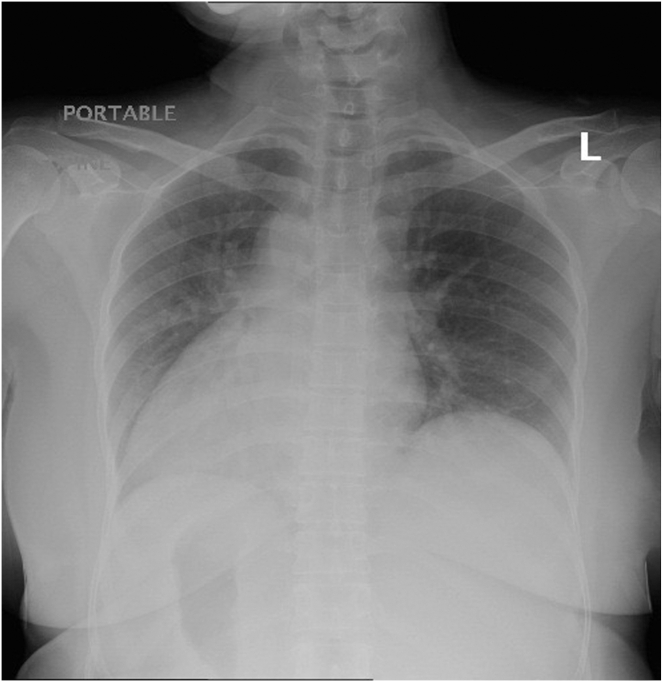

Herein we report a case of a 50-year-old woman presented with epigastric and left upper quadrant pain. Preoperative examination revealed abnormal liver chemistries, situs inversus totalis, and multiple distal common bile duct stones with intrahepatic and extrahepatic bile duct dilatation on abdominal ultrasound. The patient underwent a successful ERCP to relieve biliary obstruction. It was performed while the patient was placed in a supine position with the endoscopist standing on the left side of the patient.